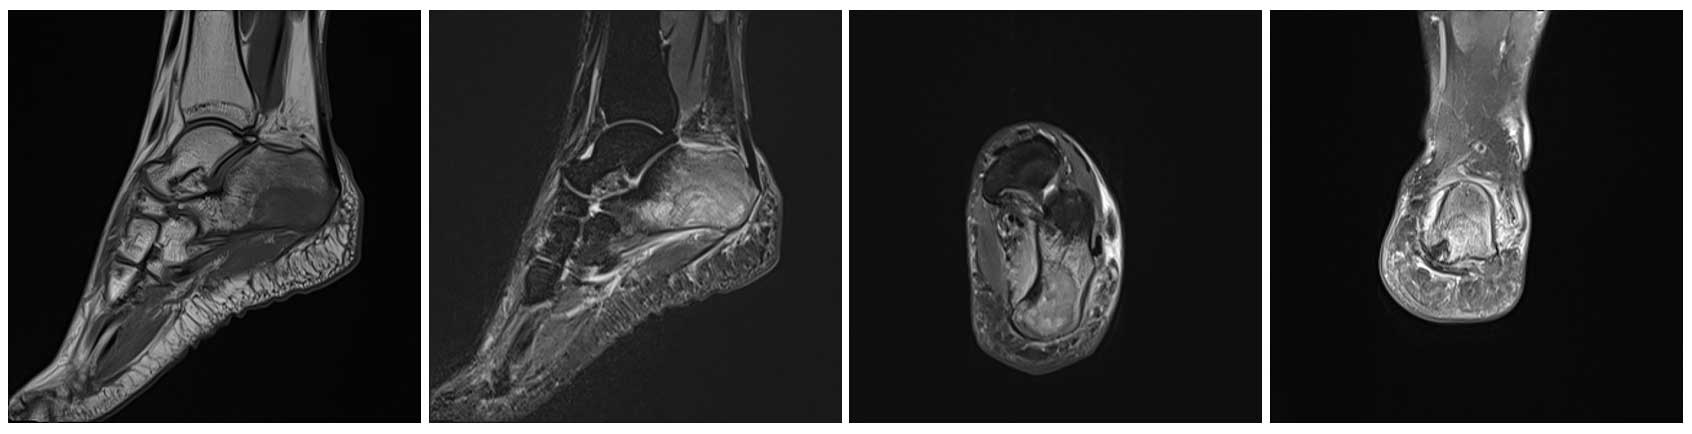

Ameliyat Öncesi: MR’da Kalkaneus inferomedial yerleşimli heterojen tümör dokusu ve çevreleyen ödem görülmekte.